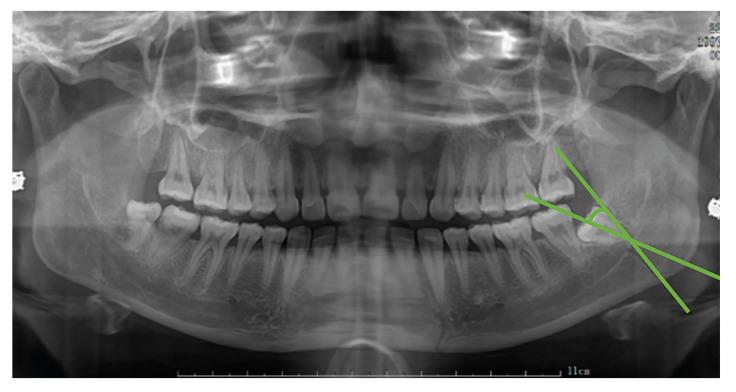

Assess the correlation between the position of the third molar (M3) and fractures of the mandibular angle and condyle using panoramic radiographs to offer valuable data references for oral clinical research.

A retrospective cross-sectional study was undertaken, involving the collection of 409 cases of mandibular fracture in the Yanbian University Hospital. The case records and panoramic radiographs of mandibular angle fracture (78 cases) and condylar fracture (106 cases) were evaluated.

In the comparative analysis between the mandibular angle fracture group and the condylar fracture group, statistical significance was observed in the variables of M3 existence (P = 0.002), eruption of M3 from the alveolar cavity (P = 0.003), P&G position classification (P = 0.001), deep impactions (Classes IC, IIC, IIIB, and IIIC) (P < 0.001), and the presence of impacted M3 in both groups (P < 0.001).Regarding M3 roots, the mandibular angle fracture group exhibited the highest prevalence of multiple roots at 75.4%, surpassing the 64.6% observed in the condylar fracture group. The prevalence of proximal angles in the mandibular angle group and the condyle group was the highest, accounting for 64.6% and 61.5%, respectively. The percentage of M3 in the two groups was 80% and 43.1%, respectively, with a significant difference (P < 0.001).

Impacted mandibular third molars (M3) elevate the risk of mandibular angle fractures, while their absence or normal eruption reduces this risk and protects against condylar process fractures. The fracture risk is influenced by the M3's position: P&G Class II and Class B impactions, where M3s emerge partially from the alveolar bone, are significantly associated with mandibular angle fractures. In contrast, the absence of M3 or its placement in P&G Class I and Class A positions tends to correlate with a higher incidence of condylar process fractures.